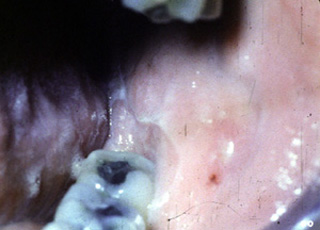

Este paciente estaba recibiendo un diurético para el tratamiento de la hipertensión. Tres años después de la iniciación de la terapia el paciente desarrolló ulceraciones del mucosa bucal y lengua. En esta lesión erosiva  se observa una placa blanca alrededor.

Aquí hay otra área afectada en el paciente presentado en la imagen anterior